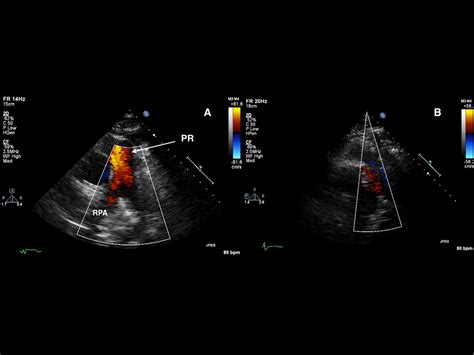

• Echocardiogram: This ultrasound test provides detailed images of the heart and can detect the presence and severity of regurgitation.